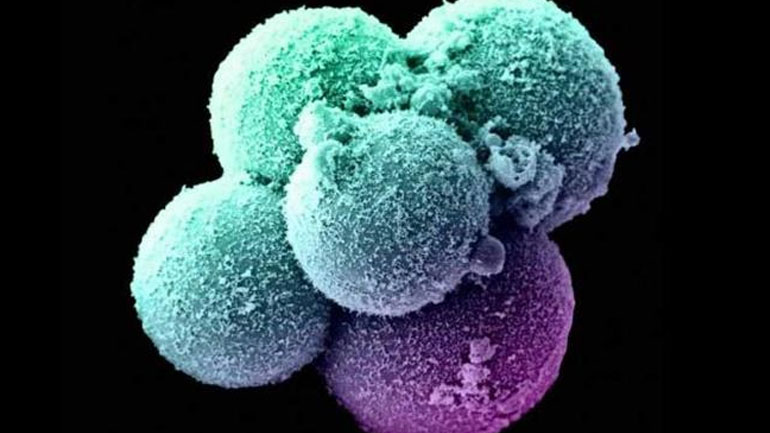

Αντιδράσεις προκαλεί το παράνομο νεκροταφείο Prima Porta στην Ιταλία, όπου βρίσκονται θαμμένα εκατοντάδες έμβρυα από αμβλώσεις. Σε κάθε σταυρό αναγράφεται το όνομα της γυναίκας που τερμάτισε...